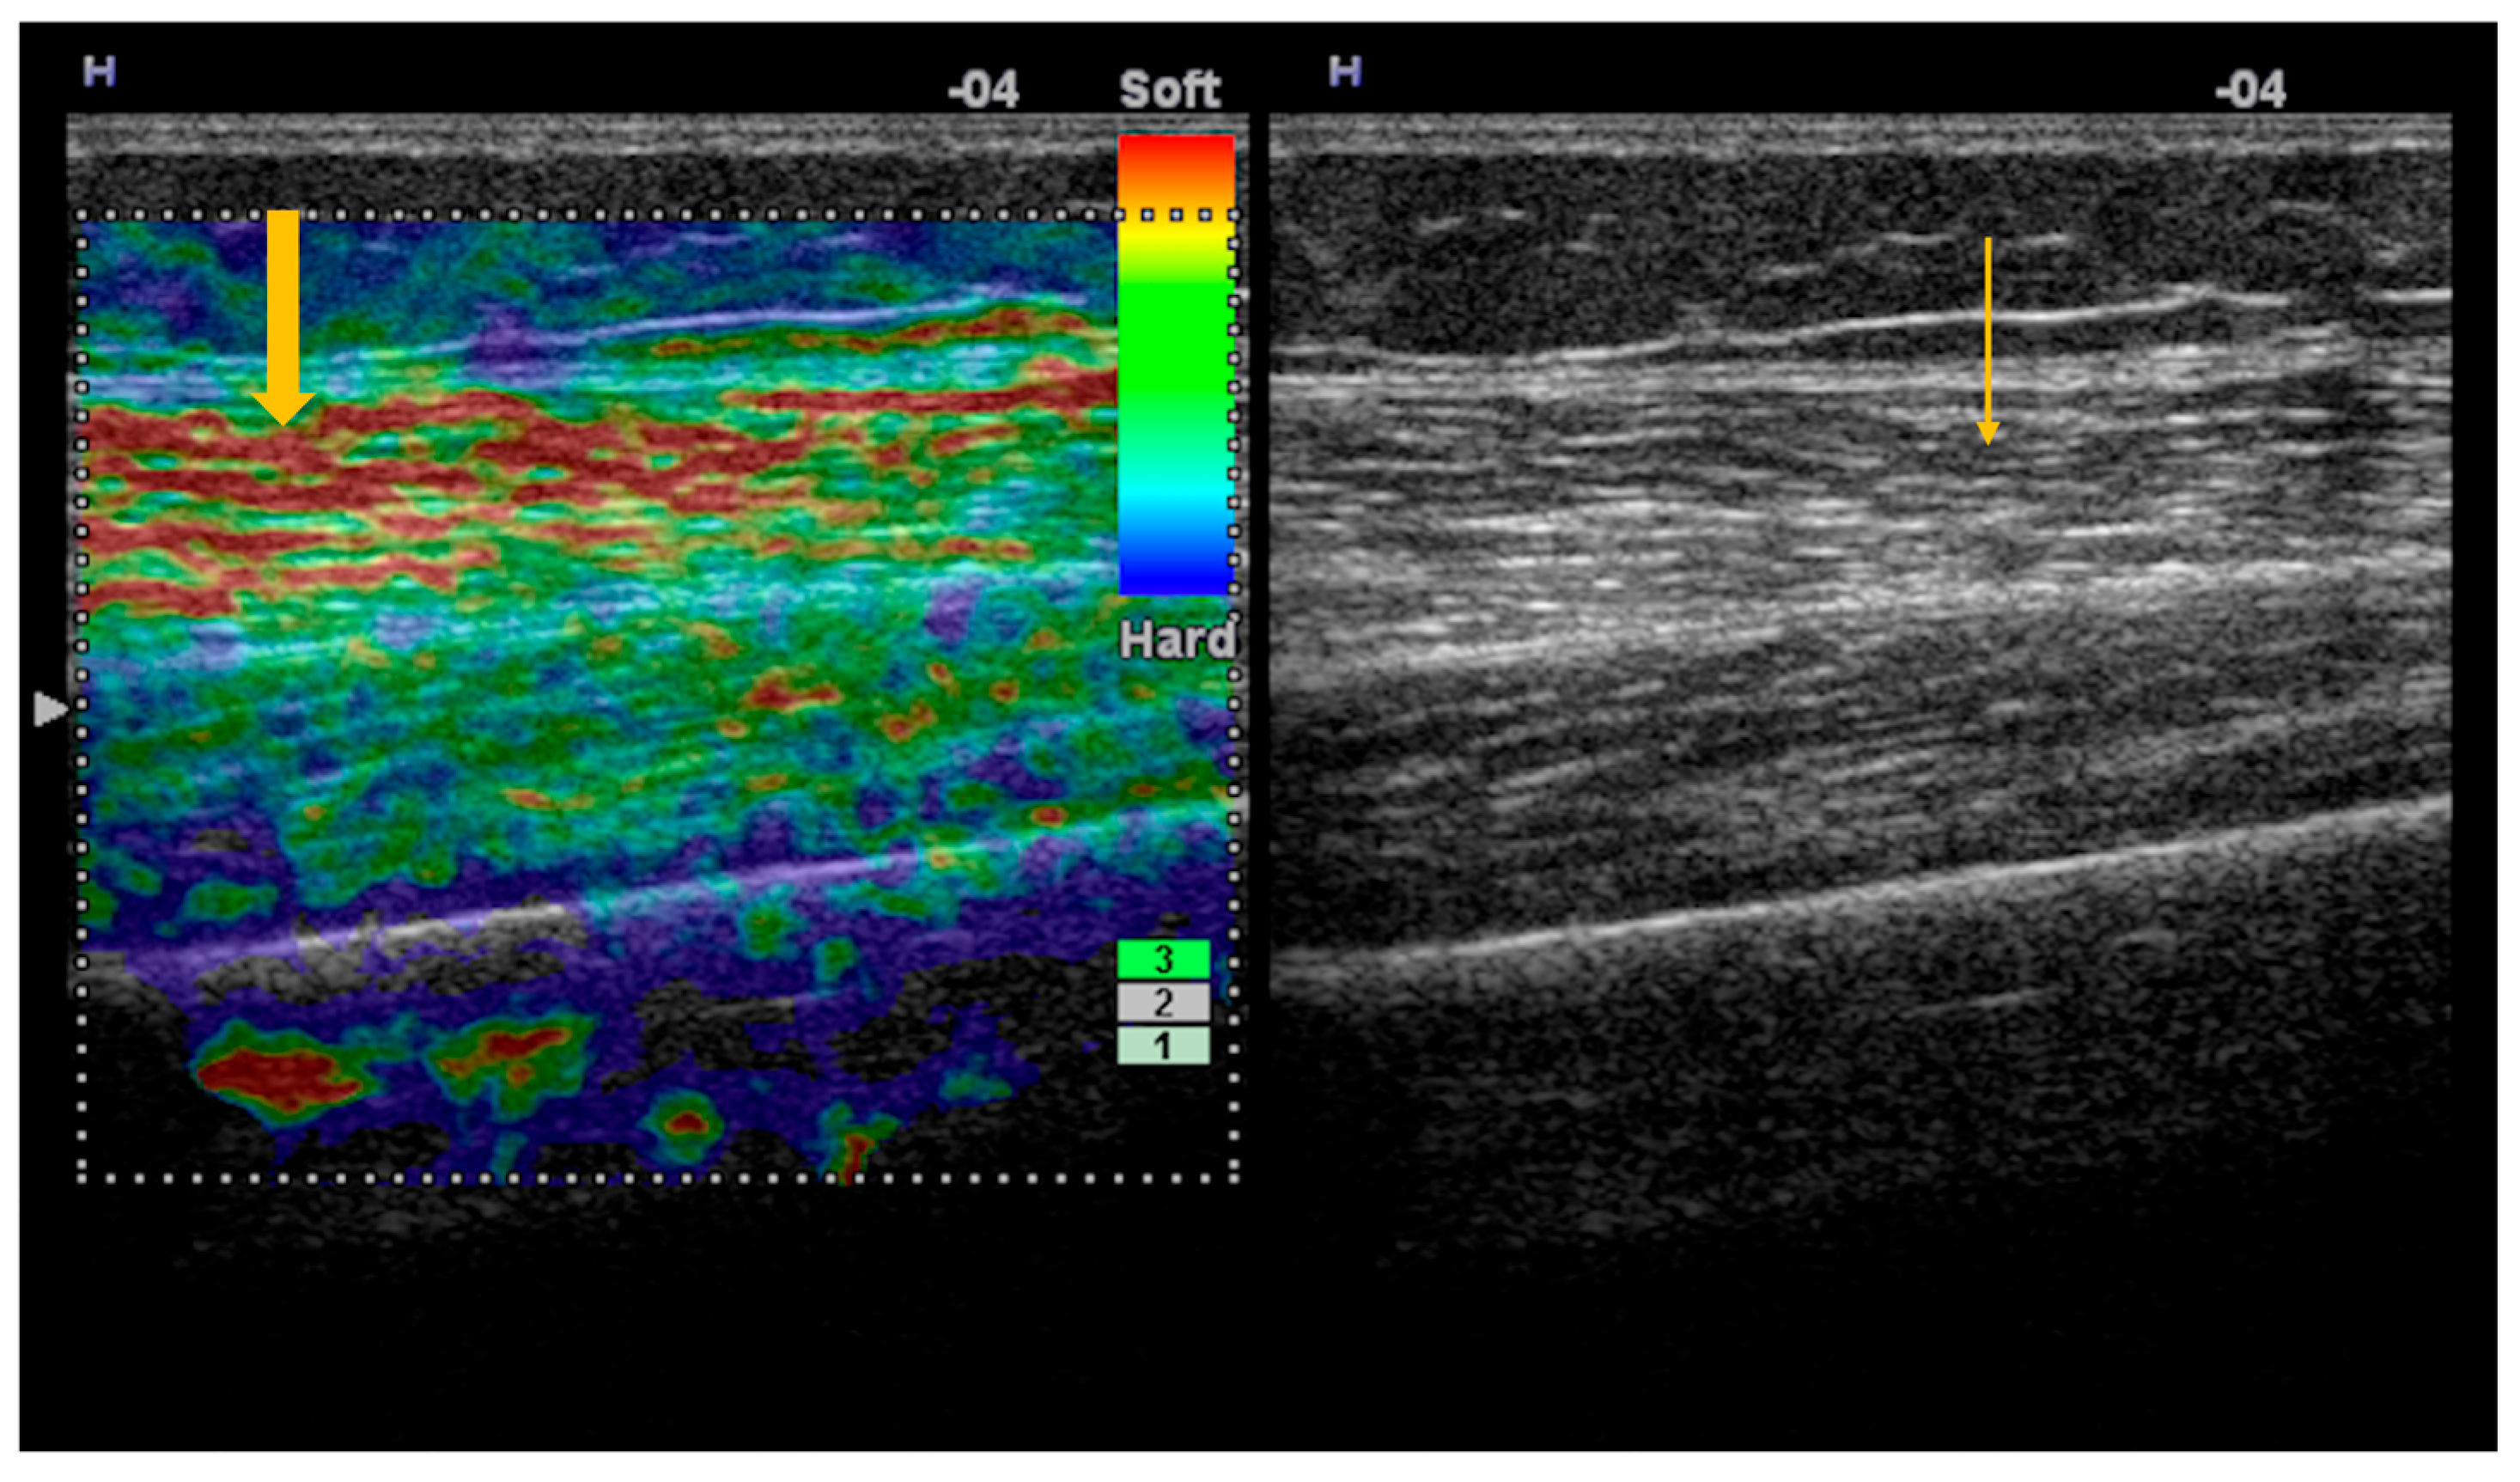

Figure 1. Strain elastography and corresponding gray-scale imaging of myositis with fatty infiltration. Strain elastography of the thigh skeletal muscle demonstrates reduced tissue stiffness, as indicated by red color coding on the elastography map (thick arrow), indicating softening of the affected muscle. The corresponding gray-scale ultrasound image shows hyperechoic muscle texture (thin arrow), consistent with fatty infiltration.